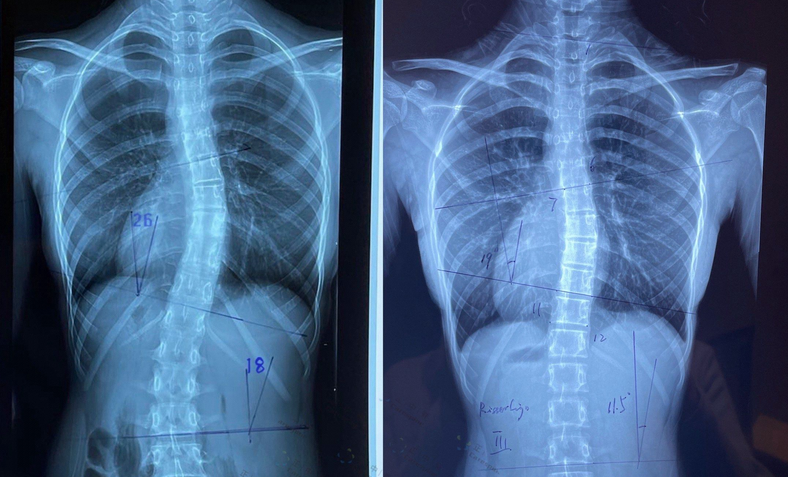

三維影像學技術在青少年特發性脊柱側彎精準診斷中的應用優化

探討生物力學評估技術在脊柱側彎診斷中的臨床價值